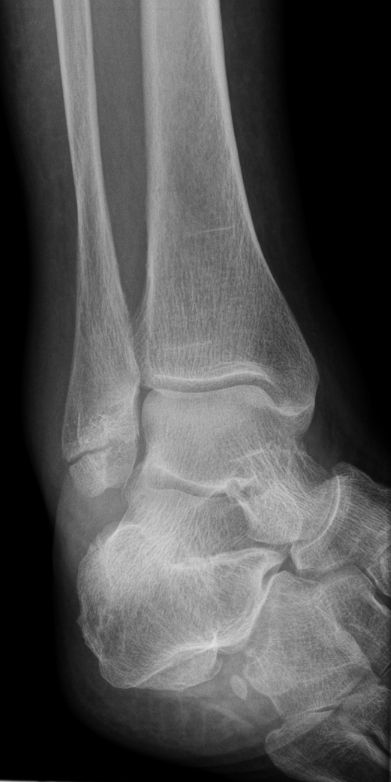

50-jähriger	Sprengstoffbeseitiger, der im Gelende ungeknickt ist.

Das Bild zeigt medial alte Absprengungen und Remodellierung nach älteren Innenbandausriss. | |||